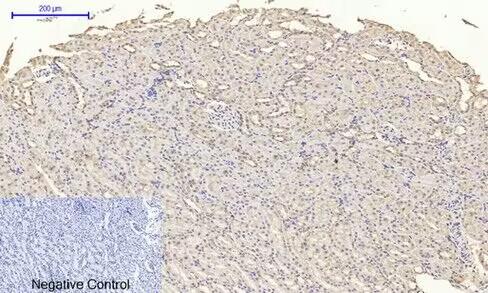

Immunohistochemical analysis of paraffin-embedded Mouse-colon tissue.

,

Immunohistochemical analysis of paraffin-embedded Rat-kidney tissue.

Immunohistochemistry: 1/100 - 1/300.